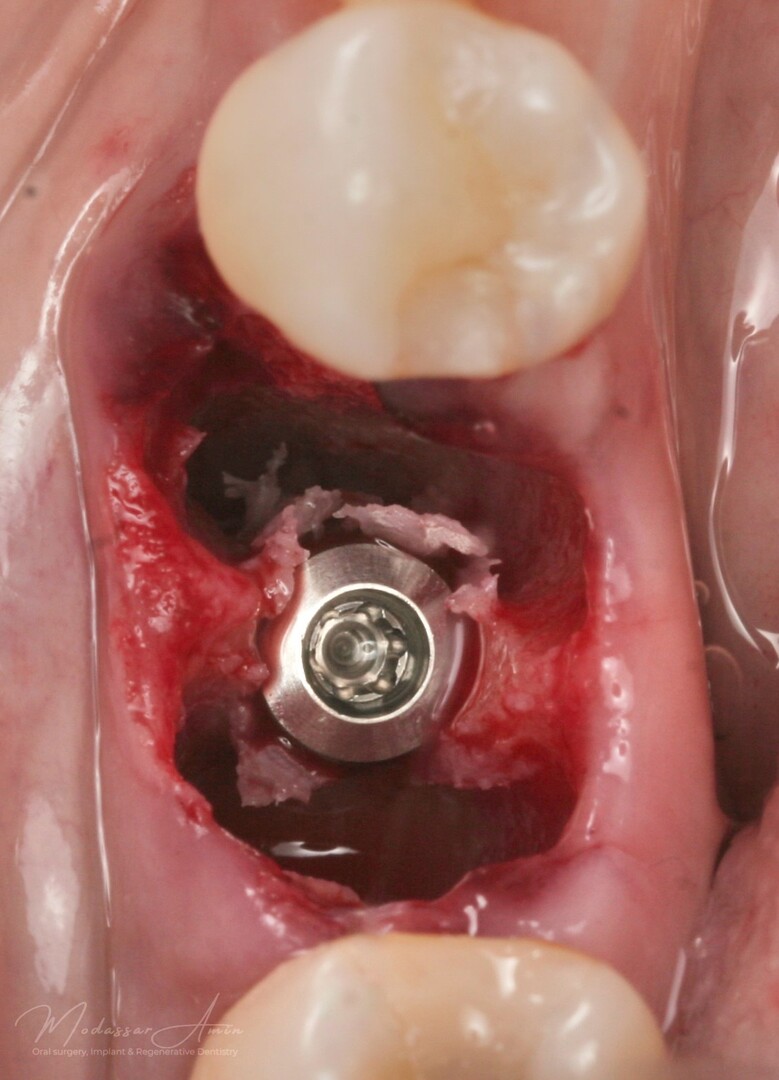

PATIENTFALL

"Pasienten presenterte med tann 46 som ikke kunne bevares grunnet en dyptgående infraksjon inn i furkasjonen. Forholdene lå til rette for en immediate implantatbehandling. Ved hjelp av Versah osseodensifikasjonsbor ble det interradikulære beinet ekspandert på en skånsom og forutsigbar måte, noe som ga høy primærstabilitet (>40 Ncm) til tross for en lokal bendefekt apikalt mesialt etter kronisk apikal periodontitt. Den gode stabiliteten muliggjorde bruk av SSA (Sealing Socket Abutment) for forsegling. På grunn av tynn bløtvevsfenotype bukkalt ble behandlingen supplert med bindevevstransplantat (CTG)"

Påbörjad expansion

Versah borr 2.3

Expanderat septum

God primär stabilitet på 40+ ncm

SSA (Sealing Socket Abutment) + CTG (bindvävstransplantat)